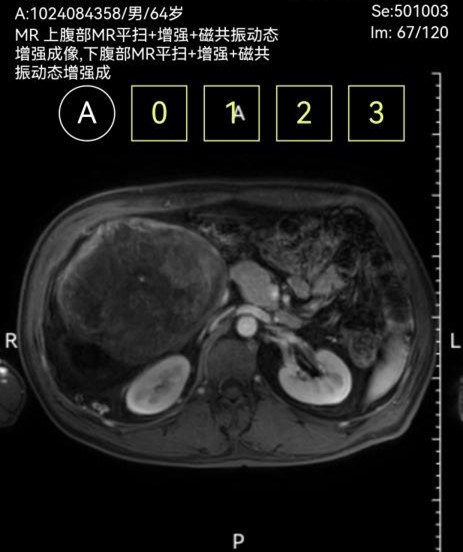

此次两名患者均因“腹部胀痛、包块及进食受限”入院,经增强CT三维重建及磁共振等检查,确诊为腹膜后巨大肿瘤。一例左侧腹膜后肿瘤,长径达30cm,重约4.8kg,紧贴腹主动脉及腹腔干,侵犯脾动脉根部及胰体尾、脾门、右肾及右肾上腺,与结肠系膜粘连紧密,挤压胃肠道引发不全梗阻;另一例右侧腹膜后肿瘤,长径40cm,重约3.2kg,侵犯结肠系膜根部血管,血供丰富,同时挤压肝门及十二指肠,存在右肾蒂损伤风险。